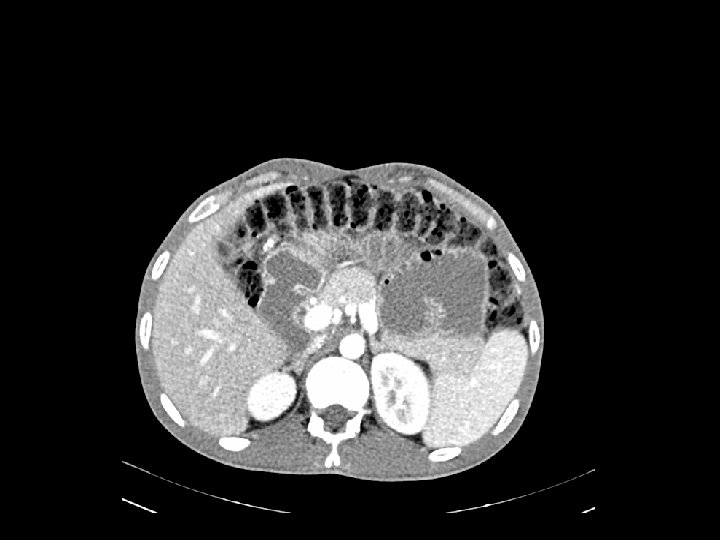

Caso Clínico 1 Urgencias (22 Agosto 2013): Dolor abdominal agudo y vómitos A la exploración destacaba abdomen distendido, doloroso a la palpación con defensa

Caso Clínico 1 Laparotomía exploradora (22/08/13) INFORME ANATOMOPATOLÓGICO PIEZA QUIRÚRGICA granyeyuno: dilataciónadenocarcinoma retrógada de asas de yeyuno, duodenodiferenciado, y gástrica con -Hallazgos: Pieza de moderadamente cambio de calibre brusco a nivel de tumoracio n yeyunal. Gran cantidad de ulcerado, que infiltra la totalidad del espesor de la muscular propia, adenopati as en la raiz del meso, mayores de un cm, de consistencia pétrea. Resto de rebasandola, y alcanzando focalmente peritoneo. Cambios inflamatorios cavidad sin hallazgos. Hi gado sin LOES. mixtos inespeci fico, asociados. Bordes de reseccio n sin hallazgos relevantes. RESECCIÓN SEGMENTARIA DE YEYUNO - Ganglios linfa ticos(25): meta stasisde adenocarcinoma (5). Linfadenitis Te cnica: Resección segmentaria de yeyuno de unos 20 cm englobando la tumoracio n en restantes. 2 la ganglios aislados separado: conlos GIA 20 60. Seccio n a nivel- de raiz del meso con mu por ltiples adenopati alinfadenitis s. Diseccio n y exe resis de las adenopati as de mayor taman o que no iban incluidas en la pieza. reactiva.